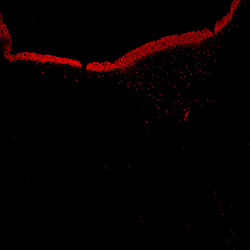

TH

13PCW human midbrain